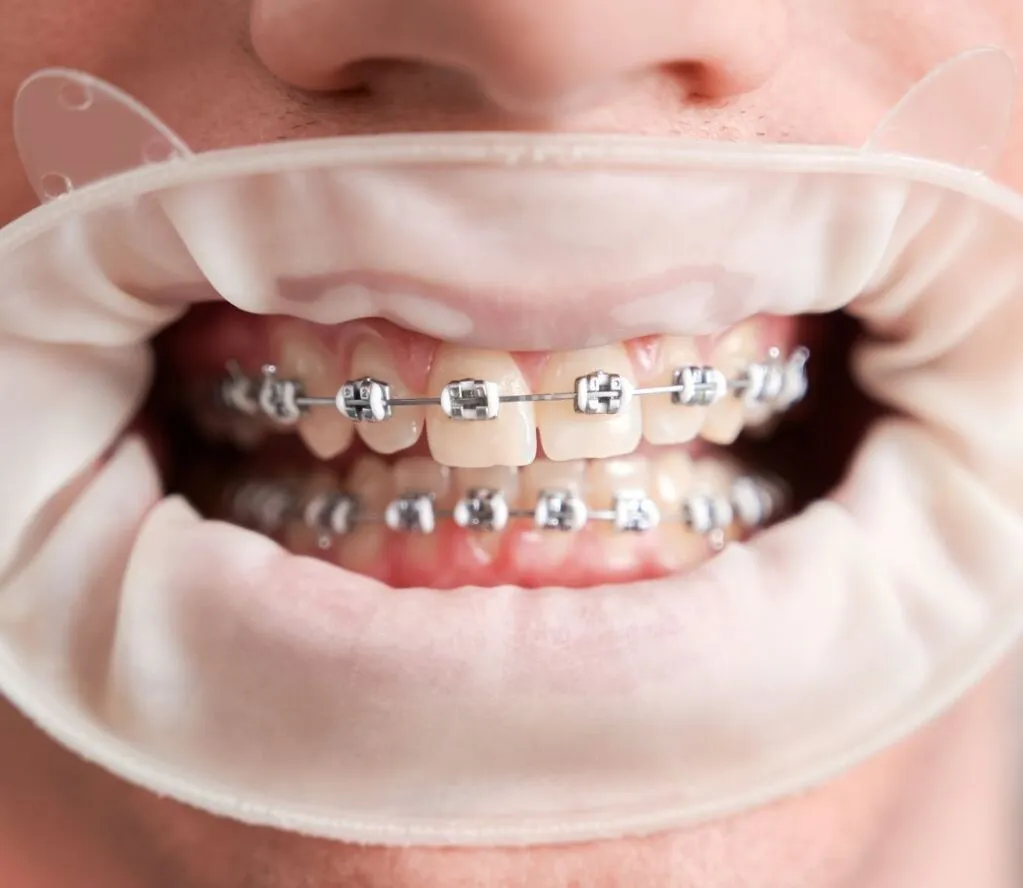

Mắc cài, vùng dưới dây cung và xung quanh đế mắc cài tạo ra các “góc chết”, ít oxy - điều kiện lý tưởng cho vi khuẩn Gram âm phát triển. Những vi khuẩn này giải phóng nội độc tố Lipopolysaccharide (LPS) và các enzyme phân giải protein, kích hoạt phản ứng viêm mạnh mẽ trong dịch rãnh lợi. Do đó, khách hàng niềng răng cần tuân thủ tuyệt đối các chỉ định của bác sĩ về việc vệ sinh răng miệng tại nhà để loại bỏ hoàn toàn mảng bám, giảm hình thành cao răng.

Khách hàng viêm lợi do không vệ sinh đúng cách